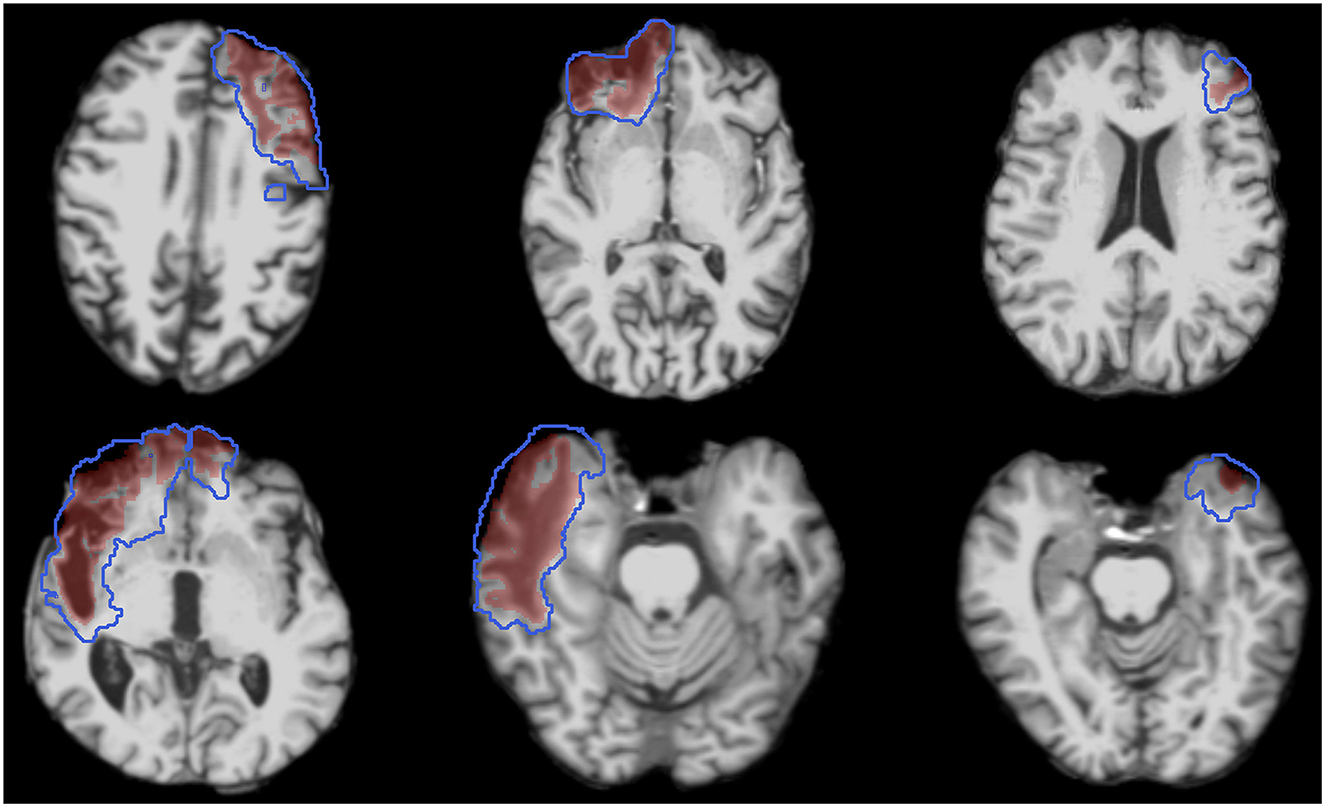

Figure 3. T1w images from Visit 1 of six representative subjects demonstrating the heterogeneous nature of lesion size and location. Images are overlayed with the ground truth lesion segmentations from Visit 1 (red shaded regions) and Visit 2 (blue outlined regions).

The 24 longitudinal participants ranged in age at Visit 1 from 33 to 73 years old, with a median age of 55.8 years (IQR = 14.3). Of these participants, nineteen were males. The 10 inter-rater participants ranged in age from 31 to 73 with a median age of 51.8 years (IQR = 22.8). Nine of the inter-rater participants were male. Additional descriptive statistics are provided in Table 4. Lesions were heterogeneous with respect to their neuroanatomic locations and were most prevalent in the anterior frontal and temporal lobes (Figure 4). For the 24 individuals studied here the ground truth lesion volume at Visit 1 ranged from 0.47 to 53.28 mL (median = 8.81 mL, IQR = 12.21 mL) and Visit 2 lesion volume ranged from 0.99 to 122.52 mL (median = 19.29 mL, IQR = 34.42 mL). For the 10 different subjects in inter-rater cohort, the lesion volume ranged from 0.93 to 29.38 mL (median = 4.44 mL, IQR = 7.53 mL).